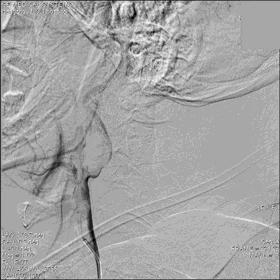

▼血栓: